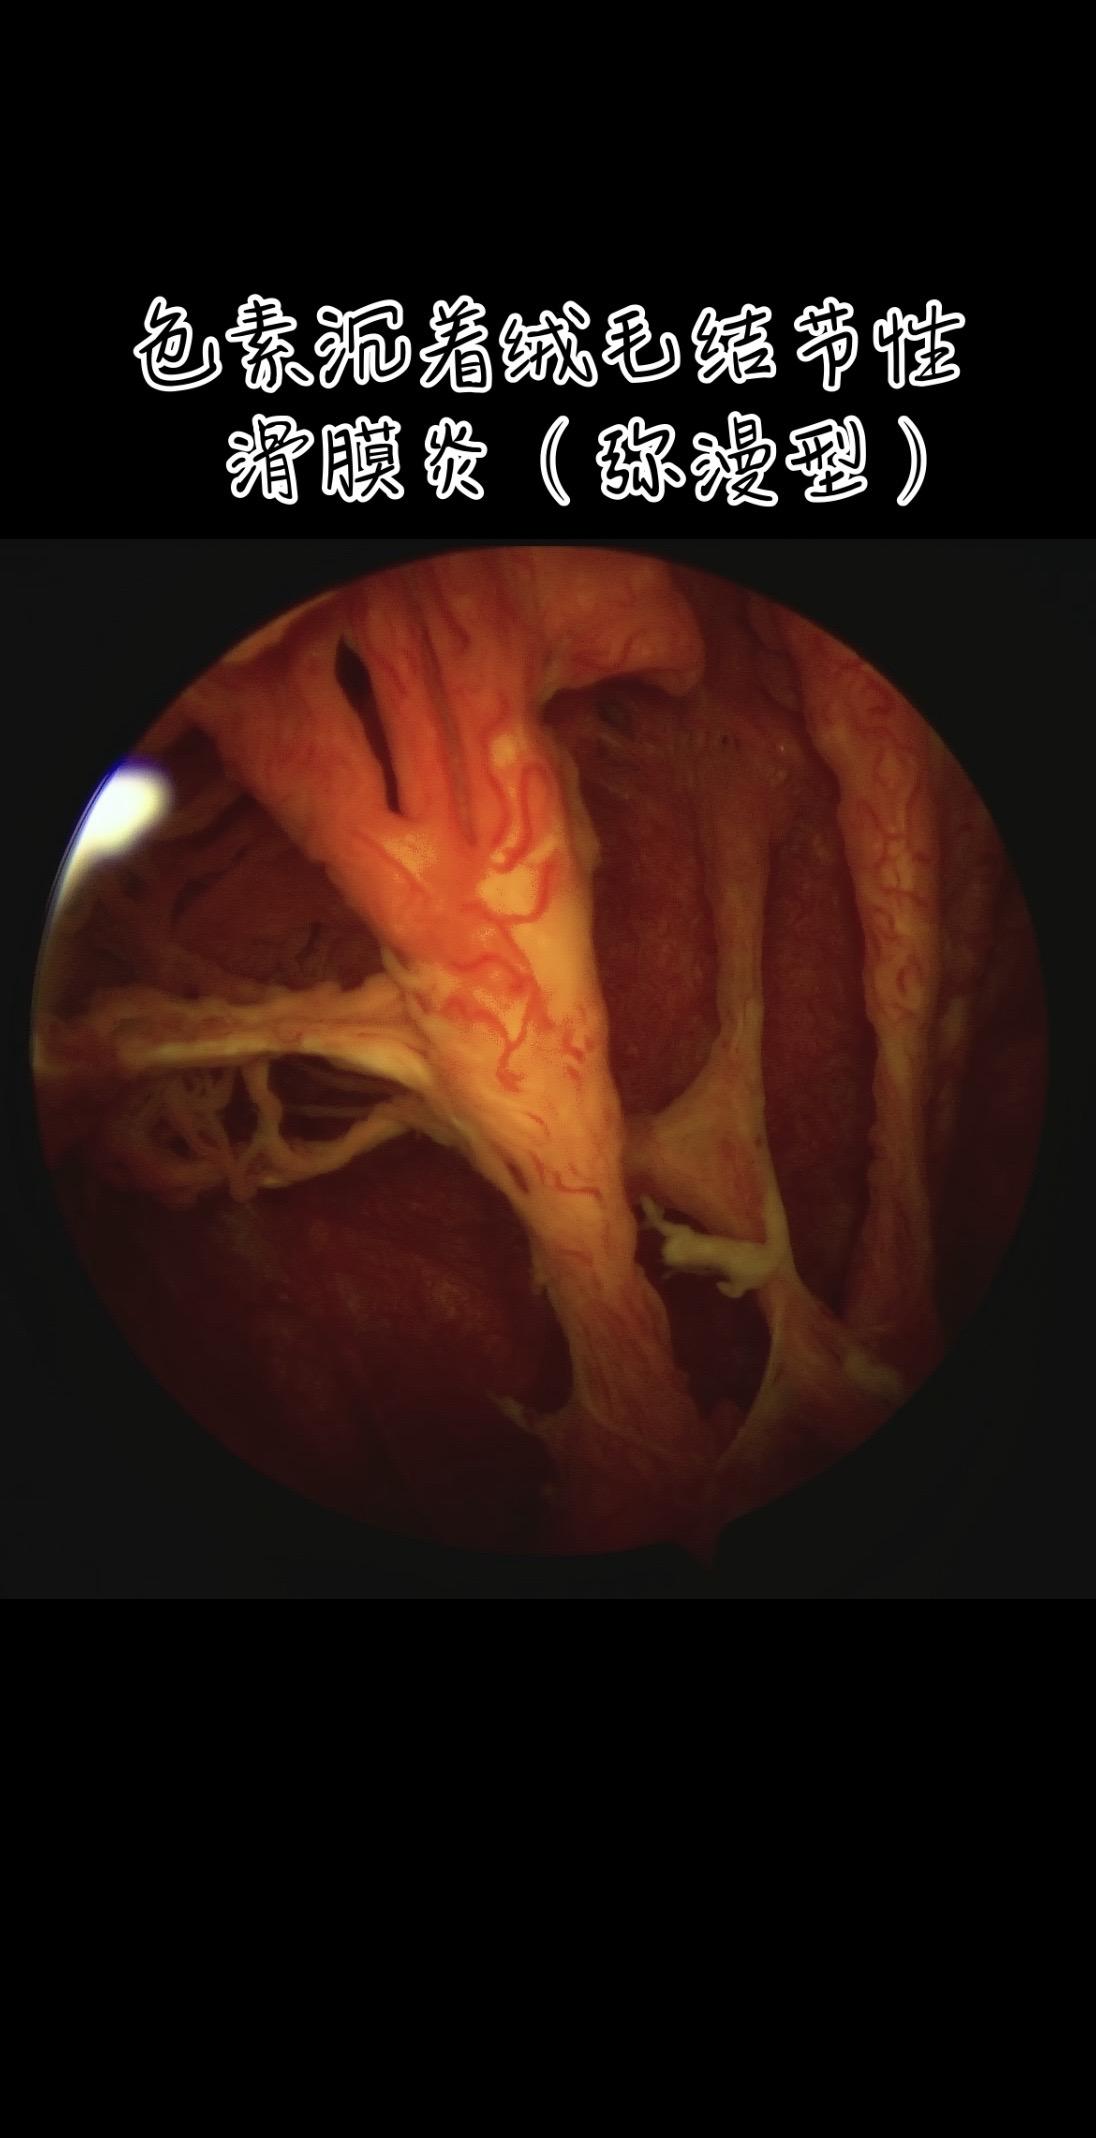

色素沉着绒毛结节性滑膜炎。膝关节反复肿,弥漫型色绒,(PVNS)